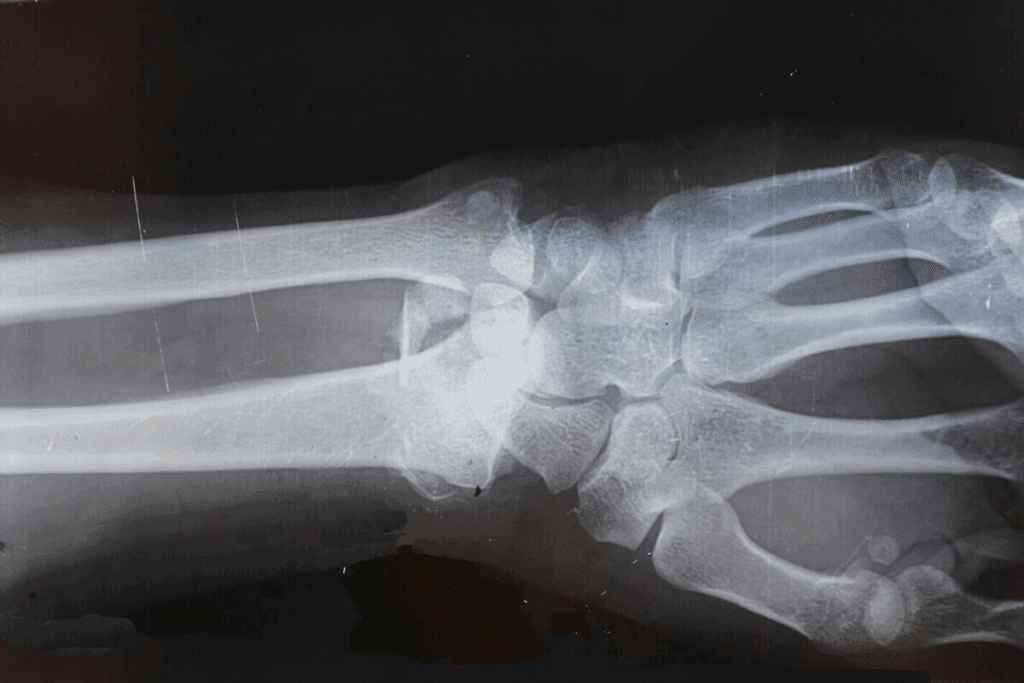

How we diagnose joints changes with each type. Synovial joints, being very mobile, need special tests. We use X-rays, MRI, and CT scans to check their health.

For synovial joints, looking at the synovial fluid and capsule is important. Fibrous joints need checks on the fibrous tissue. Cartilaginous joints focus on the cartilage’s health.